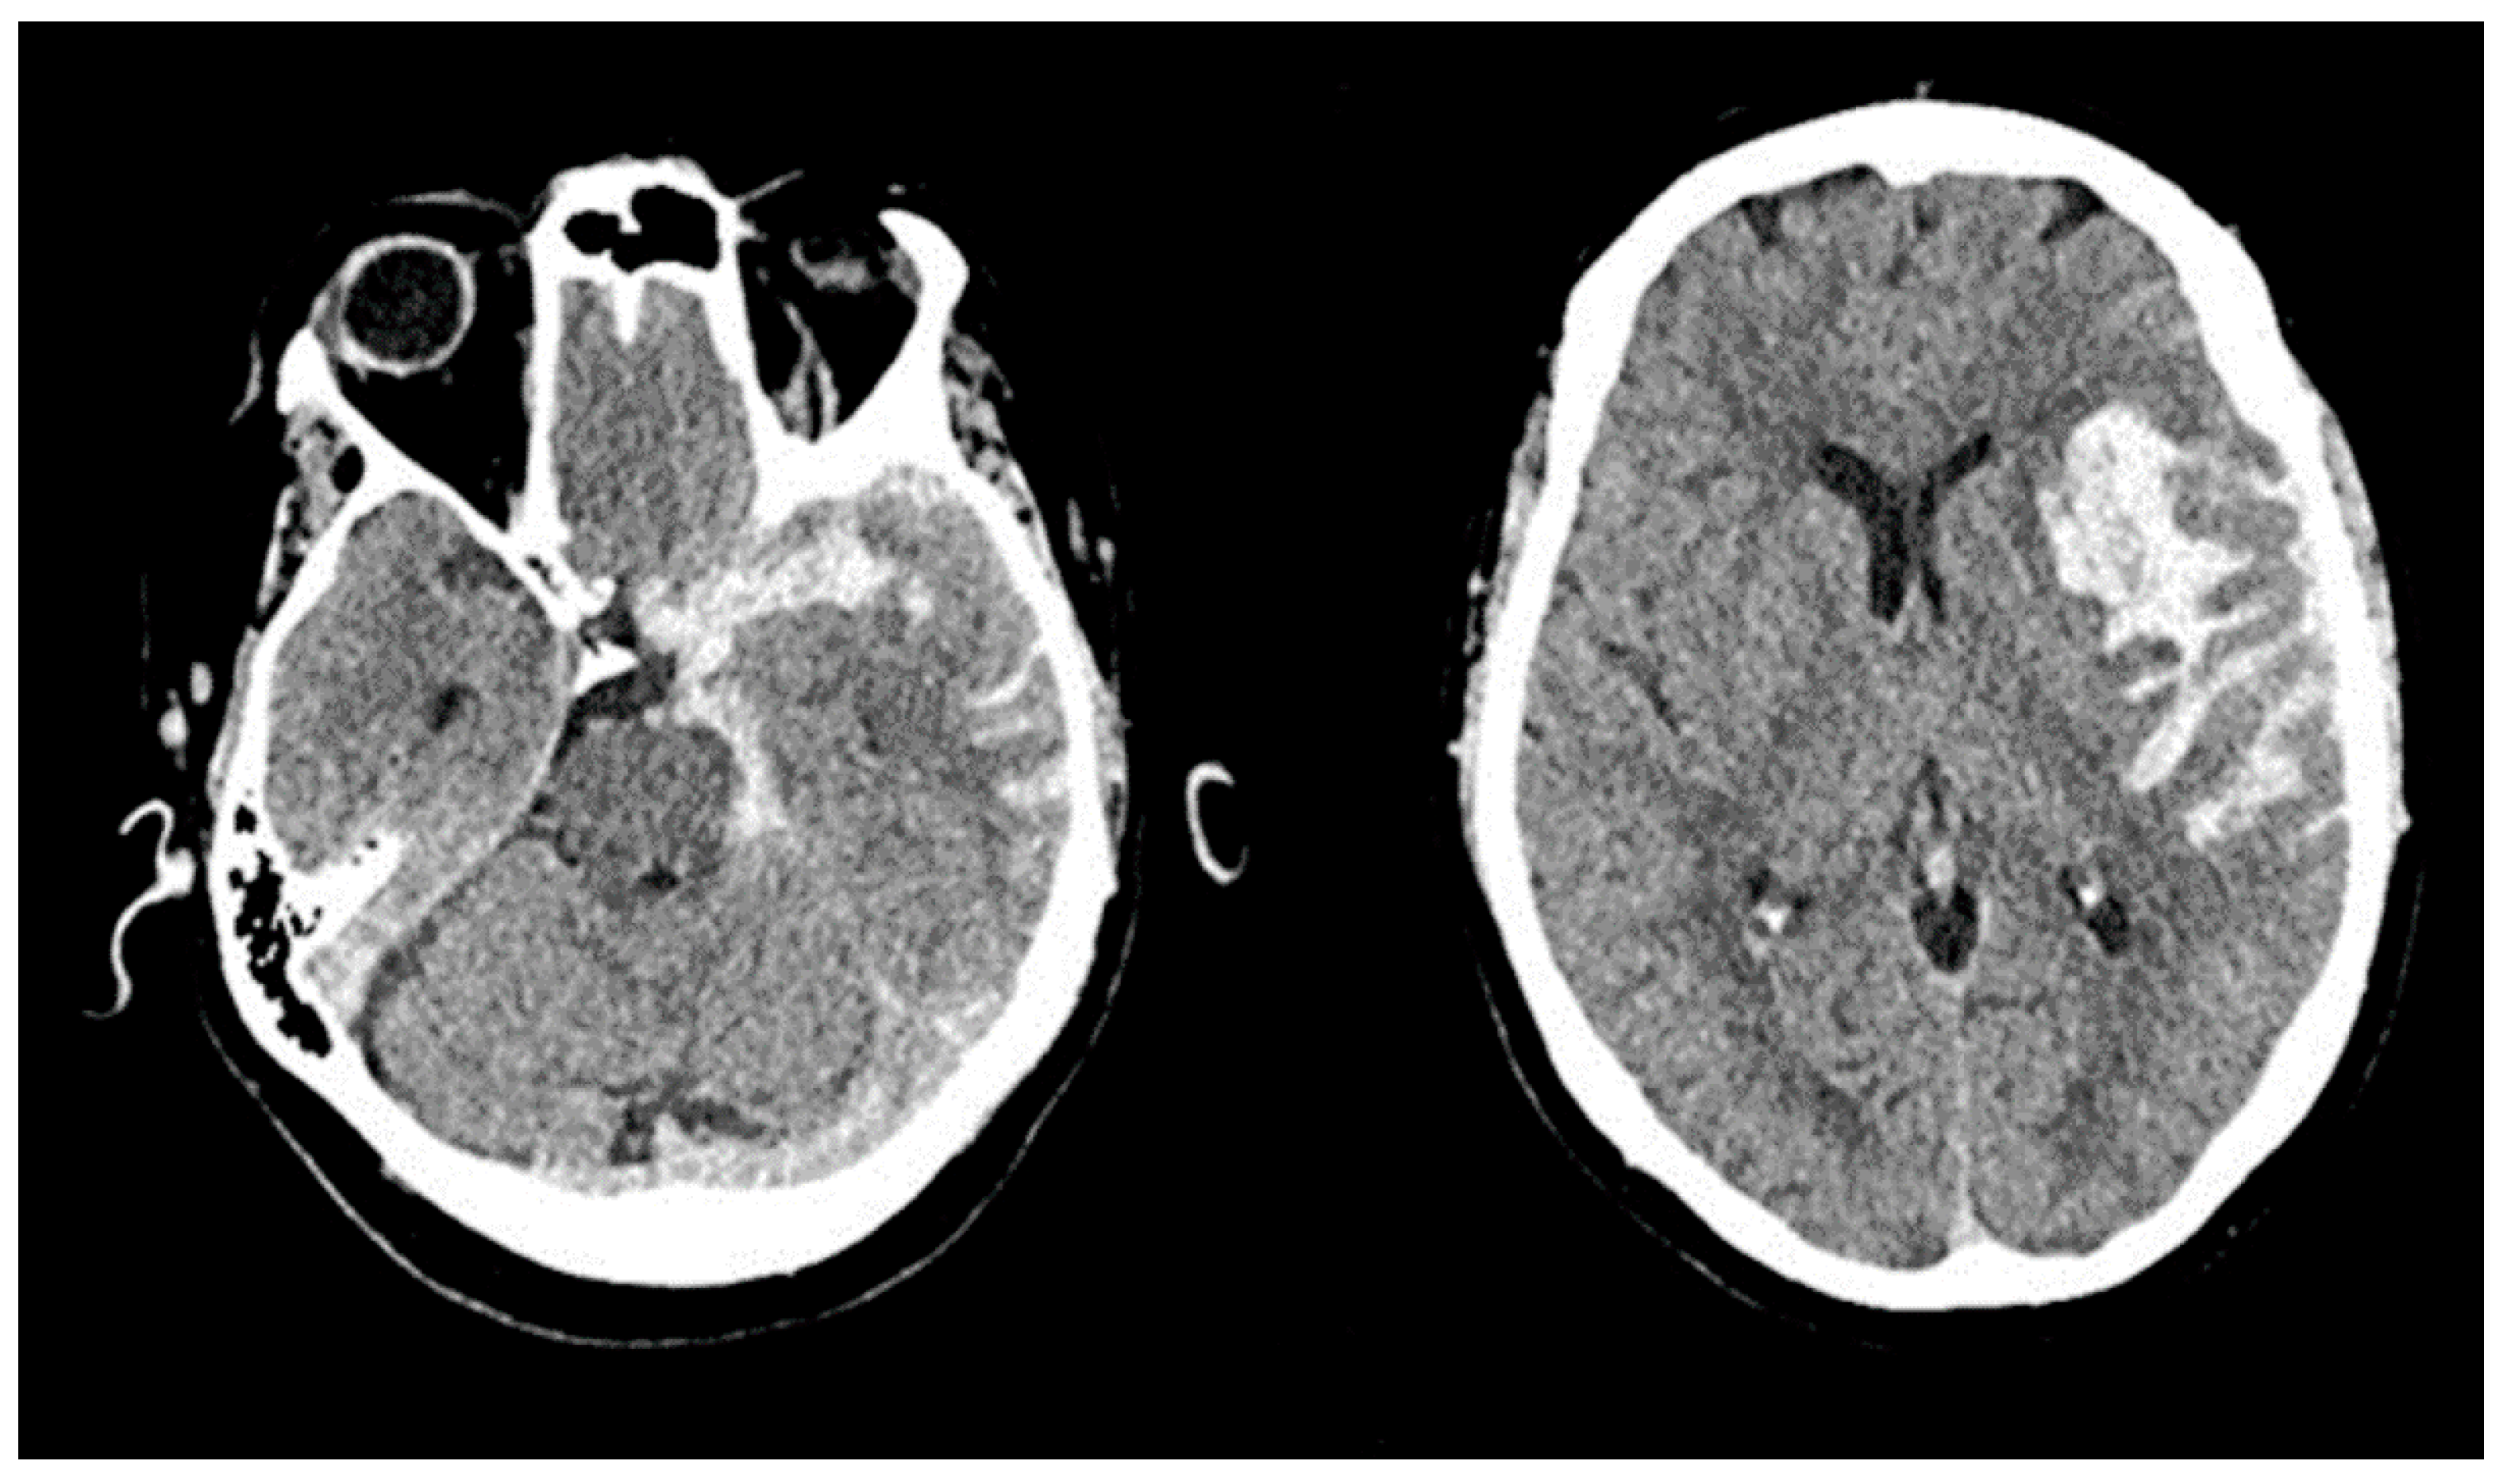

3.1. Case 1

3.2. Case 2

3.3. Case 3